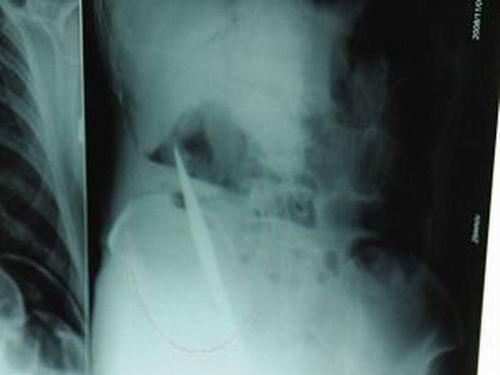

X光片上,尖刀清晰可見。

從男子體內(nèi)取出的尖刀足足有19厘米長(zhǎng)。

江蘇銅山一58歲男子因服毒被送到醫(yī)院搶救,可醫(yī)生采取搶救措施后卻發(fā)現(xiàn)效果不佳。后來經(jīng)細(xì)致檢查,醫(yī)生有了個(gè)驚人的發(fā)現(xiàn),該男子的體內(nèi)竟然有一把尖刀,醫(yī)生通過手術(shù)將位于其腹部右側(cè)橫結(jié)腸下緣的尖刀取了出來。這把尖刀足足有19厘米長(zhǎng)!據(jù)醫(yī)生推測(cè),這把刀應(yīng)該是從肛門推進(jìn)體內(nèi)的,不知男子為何想以如此殘酷的方式結(jié)束自己生命。由于搶救及時(shí),該男子已暫時(shí)脫離危險(xiǎn)。

昨天(11月6日)上午,記者在徐州礦務(wù)集團(tuán)總醫(yī)院重癥監(jiān)護(hù)室見到了這名男子,目前他雖然已經(jīng)恢復(fù)了意識(shí),但還不能開口說話,需要呼吸機(jī)輔助呼吸。據(jù)醫(yī)生介紹,4日中午12時(shí)左右,這名男子因服毒輕生被緊急送到醫(yī)院進(jìn)行搶救,之前,這名男子已經(jīng)在當(dāng)?shù)剜l(xiāng)鎮(zhèn)醫(yī)院進(jìn)行了近20小時(shí)的治療,但效果不佳。“病人被轉(zhuǎn)院到礦總院時(shí)已神志不清,血壓極低,處于休克狀態(tài)!本茸o(hù)人員給男子洗胃、初步處理以后,發(fā)現(xiàn)男子呼吸急促,于是趕緊給他拍片檢查。結(jié)果讓所有的醫(yī)生大吃一驚,竟有一把尖狀異物橫在該男子腹腔內(nèi)!當(dāng)天下午5時(shí)30分,輕生男子被推上了手術(shù)臺(tái)。經(jīng)過40多分鐘的手術(shù),該男子腹腔被打開,手術(shù)醫(yī)生發(fā)現(xiàn),男子體內(nèi)的金屬狀異物竟然是一把長(zhǎng)19厘米的尖刀!

醫(yī)生告訴記者,手術(shù)后,醫(yī)生在病人身上并未發(fā)現(xiàn)刀痕,最后,經(jīng)過檢查發(fā)現(xiàn),在該男子直腸處找到穿孔。醫(yī)生從醫(yī)學(xué)角度分析后認(rèn)為,這把尖刀應(yīng)該是從肛門插入直腸的。